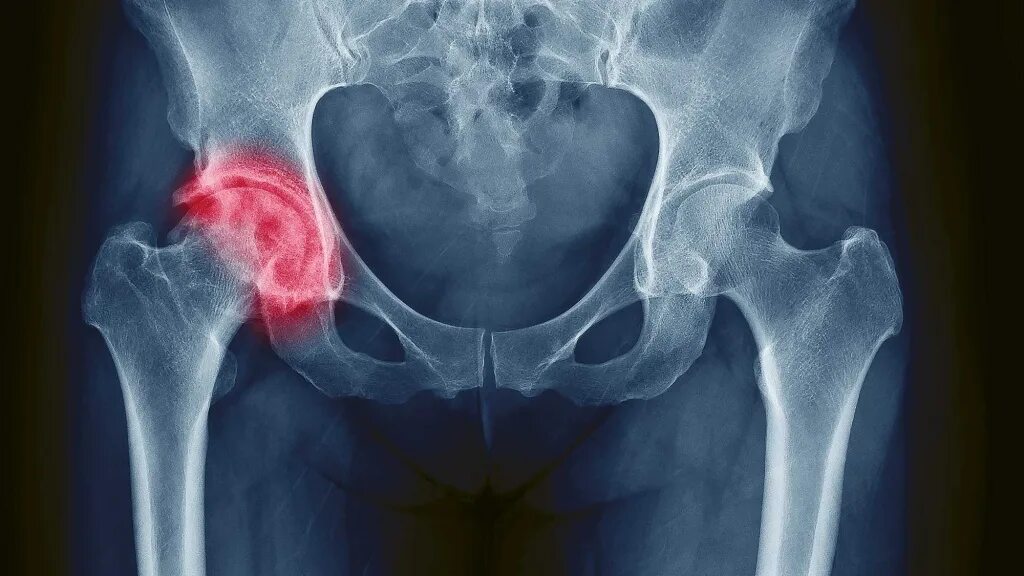

Как облегчить тазобедренный сустав